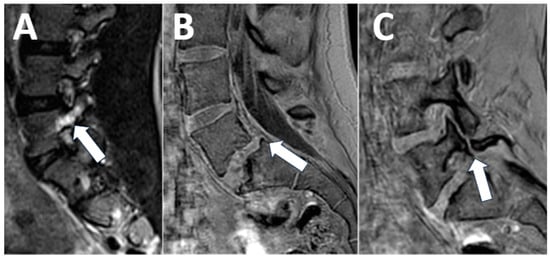

Spondylolysis is a common cause of back pain in children and adolescents, found in 12–16% [18]. The diagnosis of spondylolysis is made by radiography and computed tomography (CT) imaging [18]. However, early signs of spondylolysis, such as pedicle edema, are not apparent on CT but can be detected with MR imaging. Detection of pedicle edema from spondylolysis can help establish a diagnosis early and avoid the need for radiographs and CT imaging, which require exposing patients to ionizing radiation [20]. Our contextualized MRI protocol for lumbar back pain includes standard sequences for the evaluation of intervertebral discs and neural foramina and a sagittal T2-weighted sequence with fat suppression (STIR) to detect pedicle edema, as well as a 3D T1-weighted sequence for assessing integrity of the pars articularis (Table 2) (Figure 4).

Figure 4. Spondylolysis. (A) A 12-year-old female with back pain. The sagittal T2-weighted image with fat saturation shows left-sided pedicle edema ((A), arrow). (B,C) A 14-year-old female, competitive swimmer with back pain. Sagittal 3D T1 imaging shows anterolisthesis of L5 on S1 ((B), arrow) as well as a corticated fracture of the L5 pars articularis consistent with spondylolysis ((C), arrow).